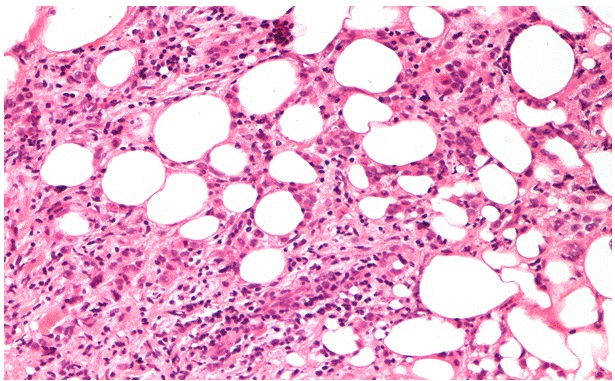

Patient 1: A 47-year-old Caucasian woman with familiar history of breast cancer, performing regular annual clinical examination and mammography as part of the screening for SHBC patients. At clinical examination, a 30 mm hard mass was detected in the left axilla, with no evident communication with the skin nor any structure referable to a nipple-areola-like complex (aberrant tissue). Imaging with mammography and high definition ultrasound revealed a hypo-echoic 25 mm mass, suspicious for a neoplasm on ectopic mammary gland. The radiological diagnosis was completed with breast MRI, which confirmed a 48×45 mm mass and an enlarged 20 mm lymph node. A core biopsy of the axillary suspicious mass was performed, and resulted in an infiltrative lobular carcinoma, triple-negative and MIB-1: 12% (Figure 1). In the orthotopic left mammary gland two more nodular masses were found (diagnosed as C4 at a fine-needle aspiration cytology) and a 14 mm lymph node was visible in the omolateral axilla. An interdisciplinary team approach recommended systemic staging with a thoraco-abdominal CT scan, that showed diffuse metastatic bone lesions (sternum, hip bones, dorsal and lumbar vertebrae, femoral bone), confirmed by a bone scintigraphy.

Figure 1. H&E sections of lobular carcinoma in Patient 1